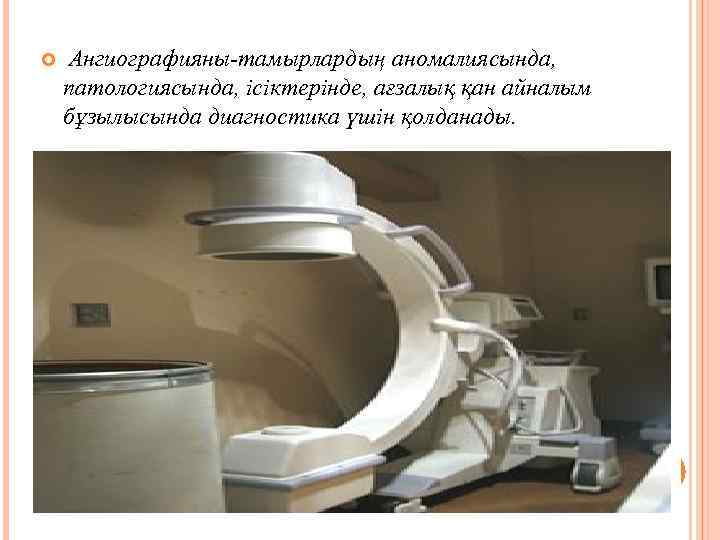

Ангиографияны-тамырлардың аномалиясында, патологиясында, ісіктерінде, ағзалық қан айналым бұзылысында диагностика үшін қолданады.

Ангиография арнайы жабдықталған рентгеноангиографиялық бөлмелерде жасалады. Ол бөлме рентгендік аппаратпен, үлкен форматта тез түсіретін аппараттармен, флюрографиялық камералармен, видеоға түсіретін аппараттармен жабдықталған.